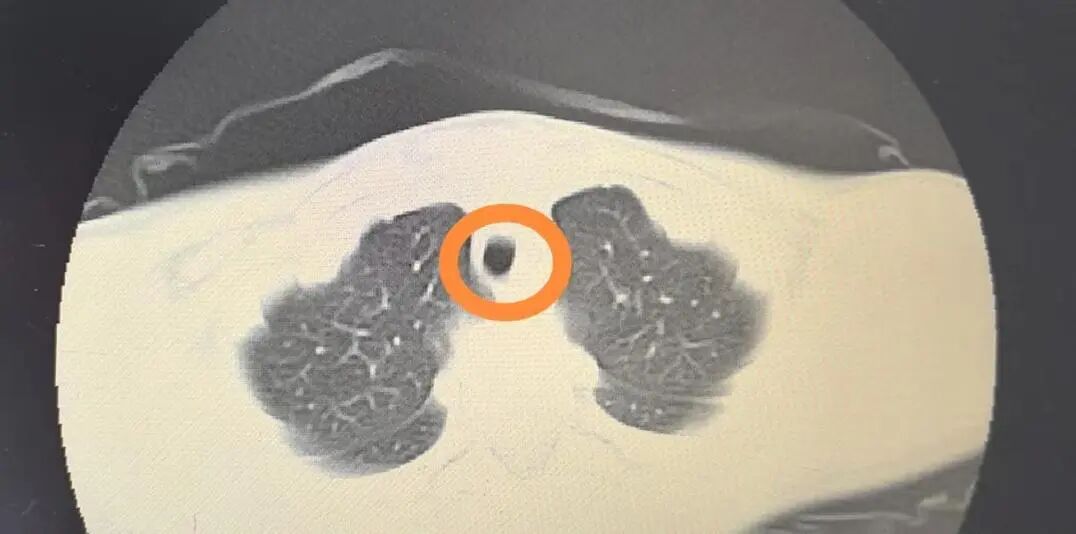

出乎意料的是,患兒的肺部CT結(jié)果提示:右肺中葉感染并局部實(shí)變不張;主支氣管內(nèi)斑片狀稍高密度影。

那是痰

栓

?還是異物?

經(jīng)科室討論,一致認(rèn)為患兒需進(jìn)一步行兒童纖維支氣管鏡檢查,了解主支氣管處的稍高密度影究竟是何物。